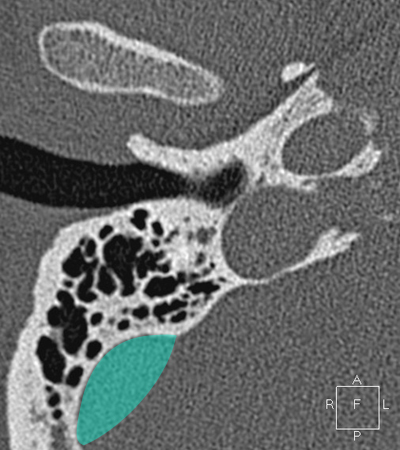

Sigmoid sinus Jugula bulb Horizontal petrous carotid Groove for tympanic (Jacobson's) nerve Facial nerve (f3), mastoid segment Anterious wall of bony EAC (tympanic bone) Mandibular condyle

Radioanatomy of Temporal bone